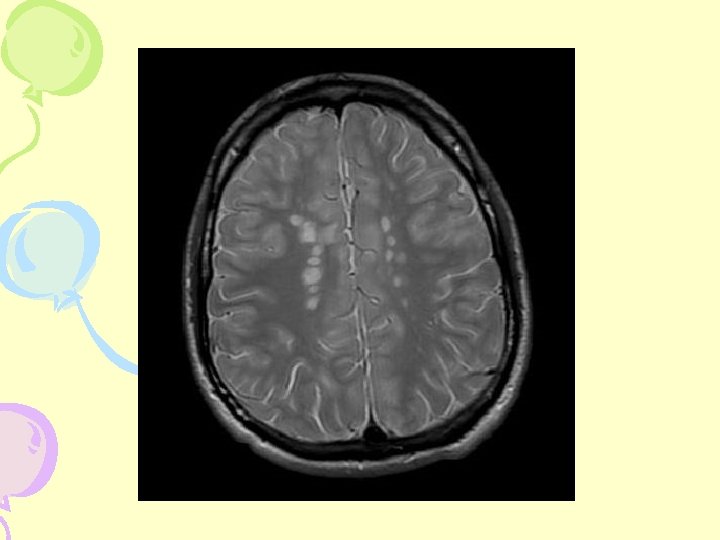

MRI - Dissemination in Space 3 of the following: • • 9 3 1 1 T 2 or 1 Gd+ Periventricular Infratentorial Juxtacortical lesion

MRI- Cerebral Hemisphere